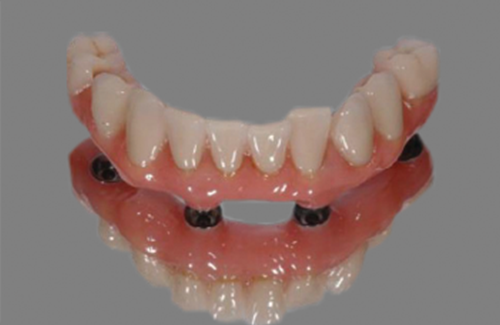

b. Position the Easy Bar chosen over the titanium cylinders ensuring that there is a gap around the cylinder so that it easily goes down as low as possible toward the tissued (does not have to touch the tissue). This will make it easier to stack the easy bars.